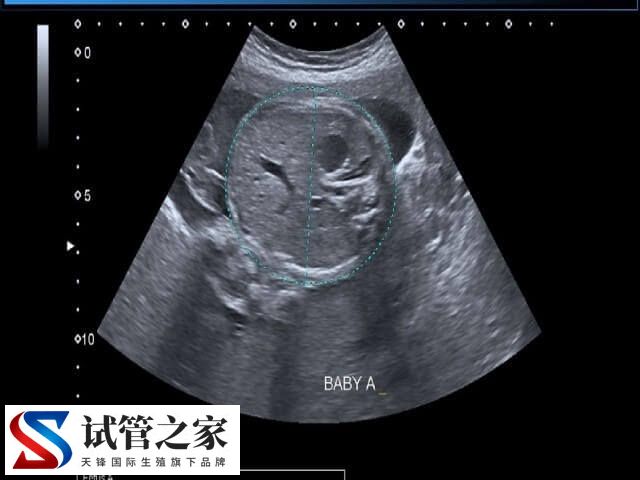

宫颈妊娠实际上就是受精卵来到了宫颈处着床发育了,这种情况极为罕见,由于妊娠位置不正确,最终也会发展成为流产,因为颈管缺少蜕膜反应,绒毛深入宫颈管壁,壁层类富含纤维结缔组织,受精卵是无法正常发育的。一般不论如何,在孕早期发生这种现象就应该及时就医了。